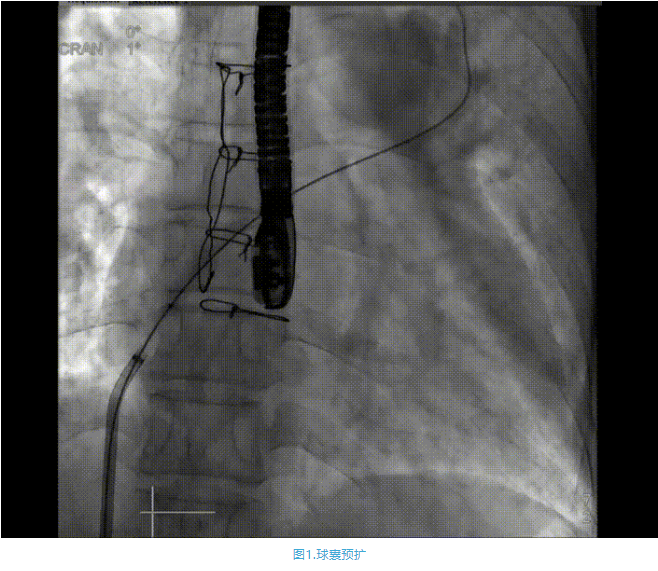

術中首先在局麻下穿刺股動脈、股靜脈,完成心導管檢查評估后轉為全麻,在食道超聲引導下穿刺房間隔,穿刺成功后將加硬導絲送入左上肺靜脈建立軌道,根據患者病情行球囊預擴張后植入6mm孔徑房間隔造孔支架,經透視及食道超聲評估支架左右盤展開良好,夾持于房間隔兩側,固定穩定、位置良好,食道彩超顯示房水平右向左為主分流,分流孔直徑符合預期大小,心導管檢查評估達到預期效果,釋放造孔支架。術后12h患者下床活動,恢復順利,擬于近日完善術后評估后出院。